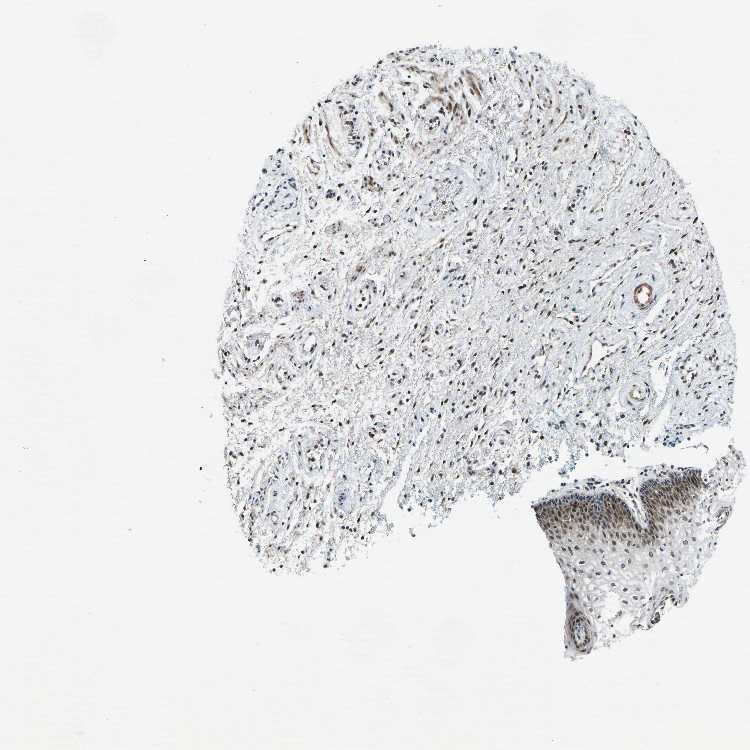

Antibody HPA018895

Squamous epithelial cells High